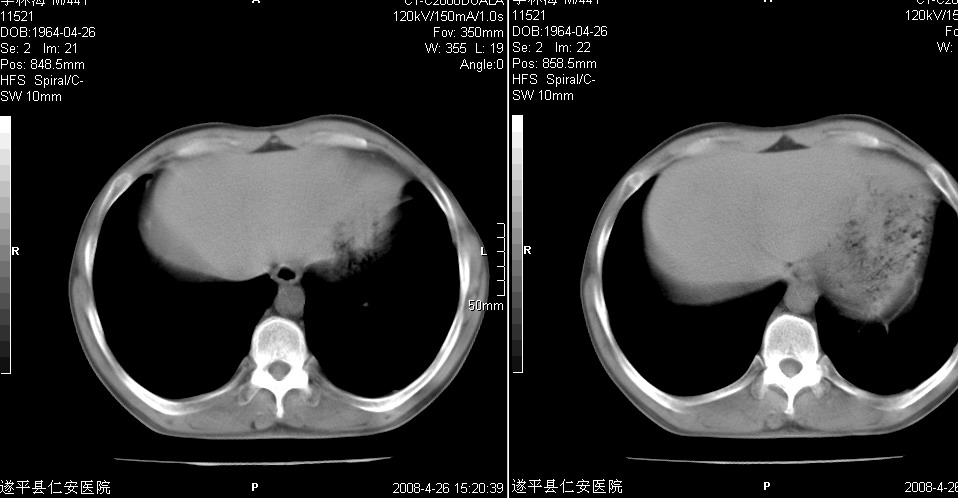

以下是引用随光逐影在2008-4-27 20:49:00的发言:[br]考虑为:1)右肺中叶及左侧下叶感染性病变。2)左肺下叶支气管扩张?建议:抗炎治疗后复查。